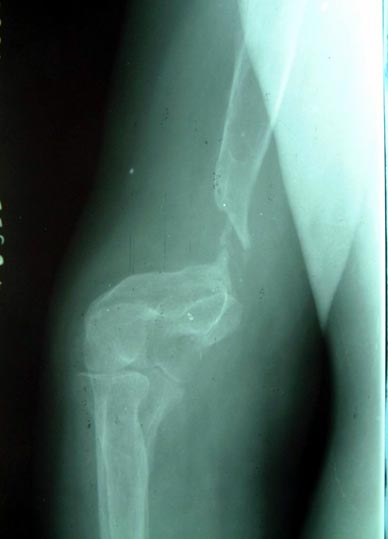

病例一、患者男性,60岁,肱骨远段开放粉碎骨折3年,骨不连,假关节形成。

图1-1我们用钢板固定骨折端提供支撑力,患者自体骨髓细胞经与异体骨和骨生长因子复合,

使没有细胞的植骨材料变成了有细胞的活骨。

图1-2 骨折在12个月后愈合,功能恢复满意。